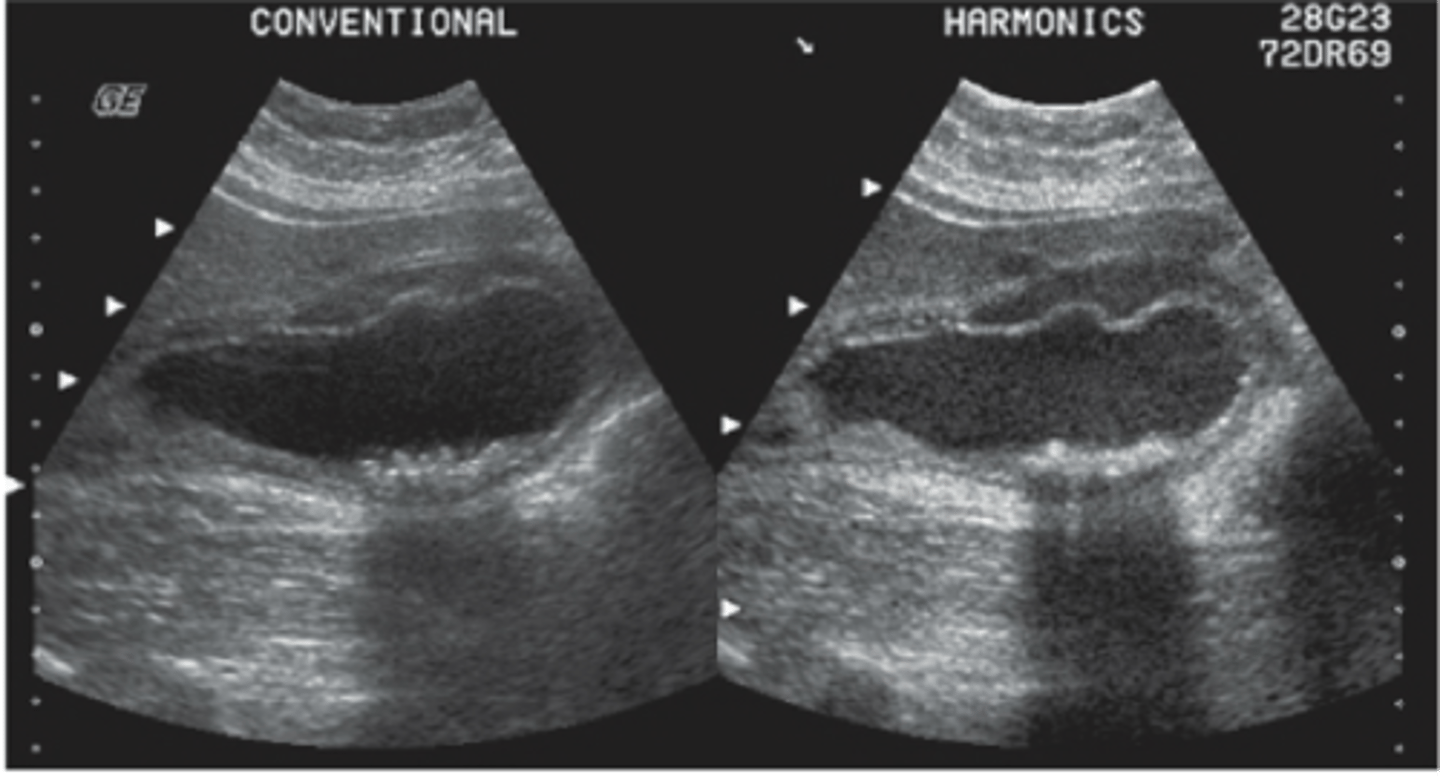

What frequency is best to scan GB?

2.5 to 5 MHz curvilinear probe

Sludge sonographic findings

GB may be packed with sludge and difficult to distinguish from liver parenchyma because it will appear isoechoic (aka hepatization).

Prominet GB with amorphous, low-level echoes without posterior shadowing located in the dependent portion of the gallbladder

Sludge is gravity dependent- will move with change in patient position